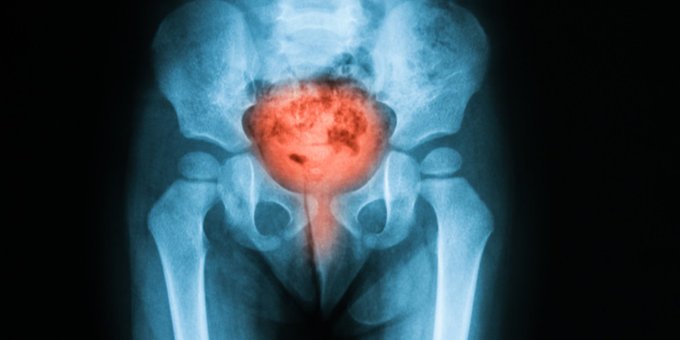

La cistitis es causada por microbios, por lo regular bacterias. Estos ingresan a la uretra y luego a la vejiga y pueden causar una infección. Entérate sobre síntomas, tratamiento y más aquí ow.ly/mkGD50xNSwf